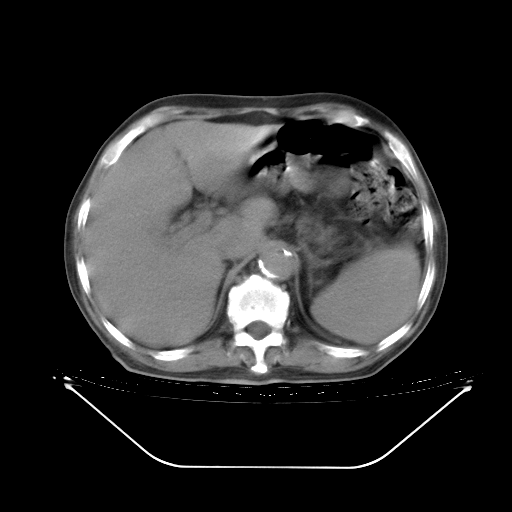

胸腹部CT,诊断意见:左上肺叶钙化灶、左侧胸膜局限性增厚并钙化、胆囊炎。描述部分肺组织呈磨玻璃样改变。

今天复查肺部CT,发现双肺广泛磨玻璃样改变。所以我把3月19日和5月9日相隔50天的肺部CT上传。请大家会诊。

5月9日肺部CT(在4月27日齐鲁医院肺部CT描述部分肺组织磨玻璃样改变,12天后肺组织广泛磨玻璃样改变)

大致读了系列胸部CT:纵隔窗无明显异常,肺窗:从4、27至今:主要是双肺中下野外带可见毛玻璃样改变,目前处于急性肺泡炎阶段,至于原因考虑1、结替组织或胶原血管性疾病所致?2、恶性疾病如恶组在肺部所致的表现或细支气管肺泡癌?3、药物或其它原因如肺蛋白沉着症所致肺泡炎目前不太可能?总之,明天就去请我院的呼吸科、感染科、血液科和临免专家会诊哈。